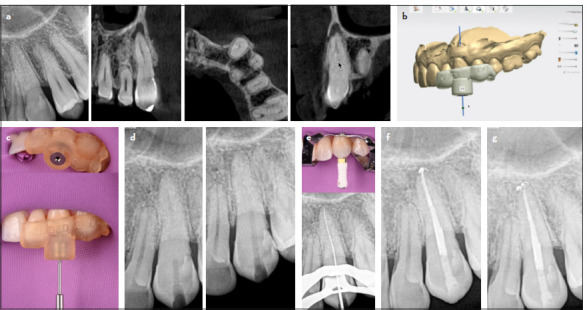

根管钙化是根管治疗的一大难题,可能导致治疗失败。困难在于进入、穿透和通过这些运河。本文报道了一系列的钙化根管成功治疗使用静态引导牙髓学。本文对11例钙化根管进行了静态引导根管治疗。样本包括四种牙齿类型,包括一个有两个管的前磨牙,使用两个模板(钻导)有效地管理。引导根管治疗是基于临床、放射学和锥束计算机断层扫描(CBCT)结果诊断的钙化根管的证据。采用高分辨率CBCT和口内扫描进行虚拟腔规划。CBCT和口内扫描叠加,虚拟滑套精确放置,以避免钻偏。制作并安装模板,低速钻孔引导入路,术中x线片监测。用k型锉平整运河,用Wave One Gold系统制备,2.5% NaOCl为灌溉剂。在所有情况下,虚拟规划的引导冠状和根管通道与3D打印模板相结合,可以通过封闭的牙髓空间进行根管定位,采用保守的进入方法,不会发生事故。这些病例表明,静态引导的牙髓治疗是一种安全准确的治疗方法,可以进入钙化管,减少工作时间,最大限度地减少牙齿结构的移除,降低医源性损伤的风险。(eej - 2024 - 07 - 106)。

Root canal calcification poses a substantial challenge in endodontic practice and may lead to treatment failure. The difficulty lies in accessing, penetrating, and negotiating these canals. This article reports on a series of calcified root canals successfully treated using static-guided endodontics. Eleven cases of calcified root canals were treated by the same endodontist using static-guided endodontics. The sample encompassed four tooth types including a premolar with two canals, effectively managed using two templates (drill guides). Guided endodontic treatment was based on evidence of calcified root canals diagnosed with clinical, radiographic, and cone beam computed tomography (CBCT) findings. A high-resolution CBCT and an intraoral scan were used for virtual cavity planning. The CBCT and intraoral scan were superimposed, and virtual sleeves were accurately placed to avoid drilling deviation. Templates were fabricated and fitted, and guided access was conducted with low-speed drilling, monitored with intraoperative radiographs. Canals were negotiated with K-files, and prepared with Wave One Gold system, using 2.5% NaOCl as irrigant. In all cases, virtually planned guided coronal and root canal access allied to the 3D printed templates allowed canal location through obliterated pulp spaces with a conservative access approach and without accidents. The cases demonstrated that static-guided endodontics is a safe accurate treatment approach to access calcified canals, reducing working time, minimizing removal of tooth structure, and decreasing the risk of iatrogenic damage. (EEJ-2024-07-106).